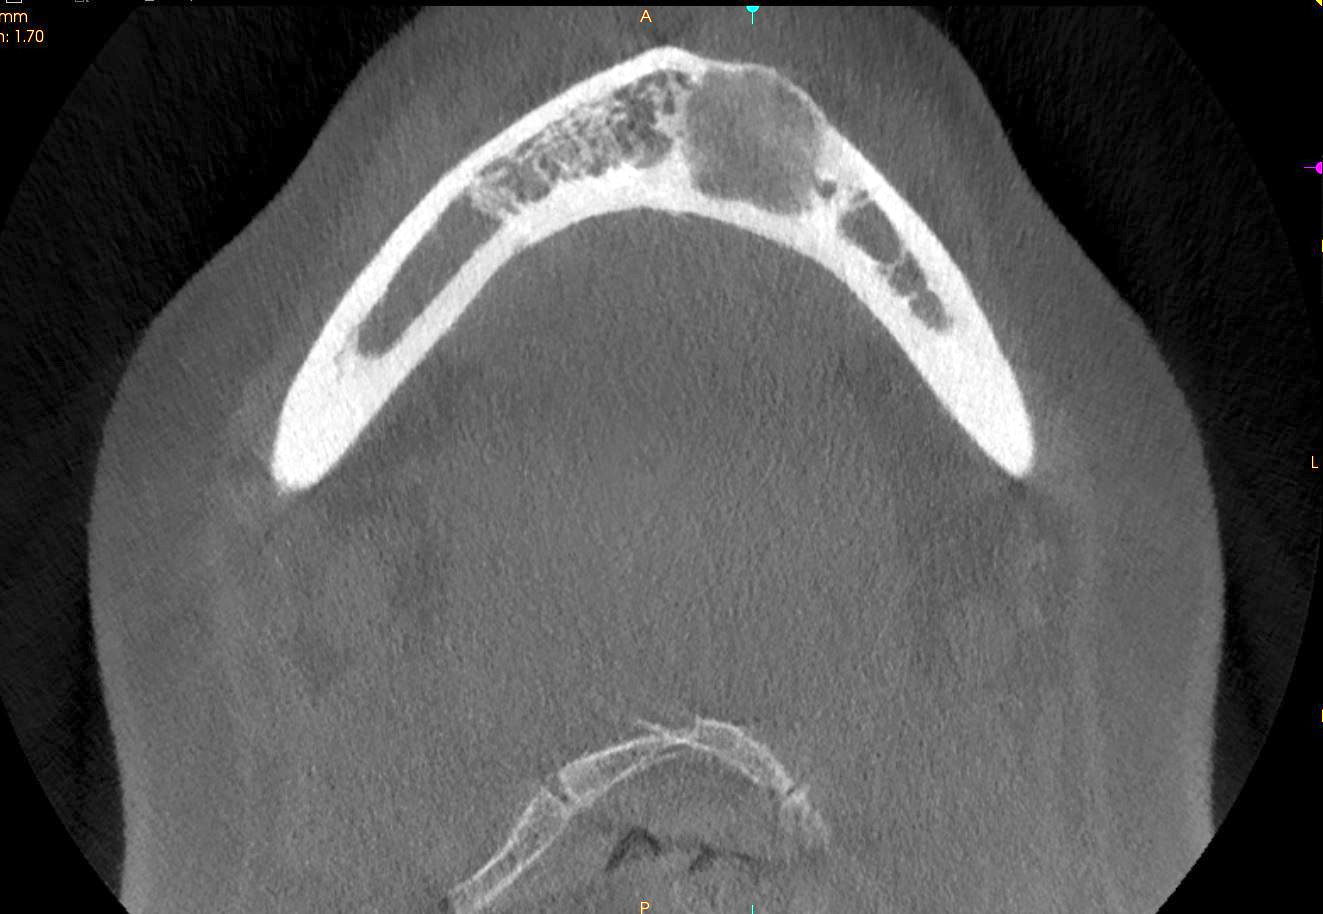

Radiology description

- Radiological findings vary according to maturity of lesion; early lesions show well defined corticated radiolucency and over time, lesion becomes progressively more radiopaque (Heliyon 2021;7:e07594, BMJ Case Rep 2020;13:e239286)

- Well circumscribed, unilocular lesion with centrifugal pattern of growth (Heliyon 2021;7:e07594)

- Can present as lesion with well defined sclerotic borders and is predominantly unilocular (BMJ Case Rep 2020;13:e239286)

- Larger lesions show expansion, thinning and perforation of buccal and lingual cortex and involvement of the lower border of mandible (BMJ Case Rep 2020;13:e239286)

Radiology images